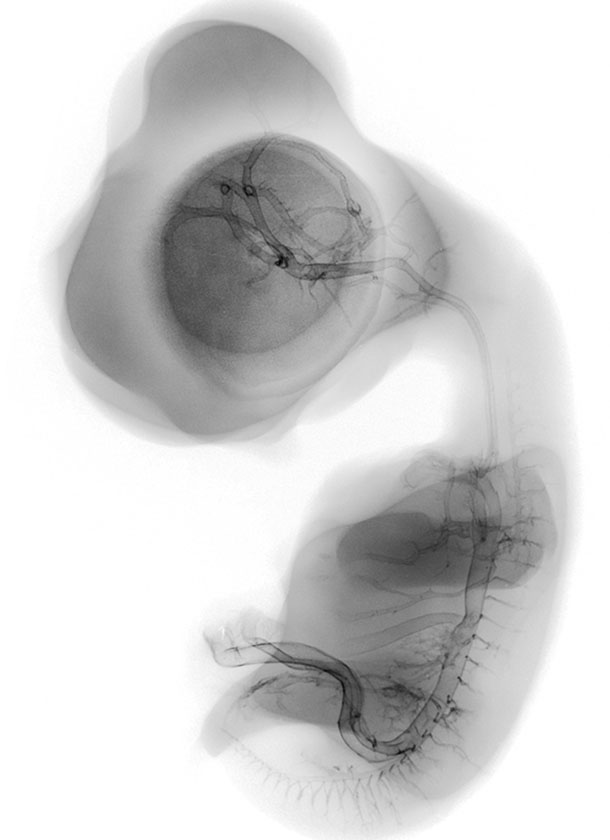

Chick Embryo Microangiography

The Chick Embryo Microangiography website is a collection of micrographs depicting the vasculature of chick embryo development from day 2.5 to day 9. The chick typically hatches at day 21. Days 2.5 to 9, as represented in this collection, correspond to Hamburger-Hamilton (HH) stages 16 to 35. Hatching typically occurs at HH stage 46. The collection of images is intended to serve students, researchers, and the general public interested in viewing, studying and teaching animal development.

Composite Image of numerous chick embryo x-ray micrographs